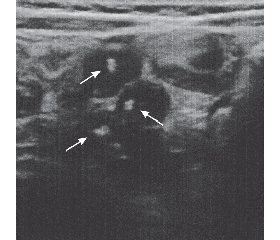

Ультразвуковое исследование (УЗИ) органов брюшной полости выявило увеличение печени, ее край выступал из-под реберной дуги на 30 мм. Селезенка не увеличена. Лимфоузлы брыжейки увеличены от 10 до 12 мм, содержали множественные кальцинаты (рис. 1, 2).